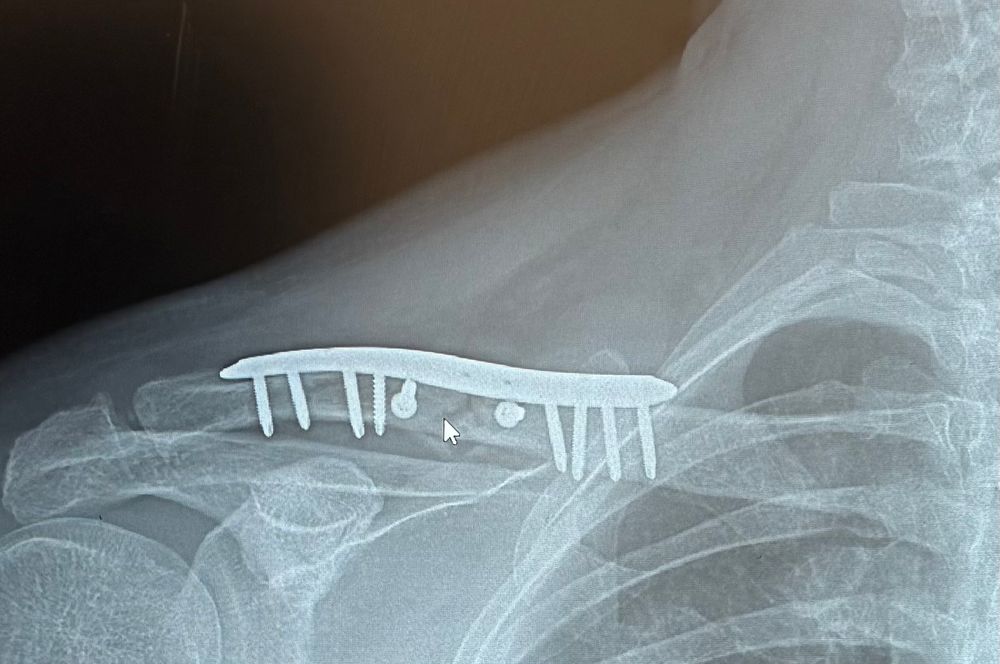

So far in this month of August I have had pneumonia and been hit by a truck while motorcycling and needed to have my clavicle surgically repaired.